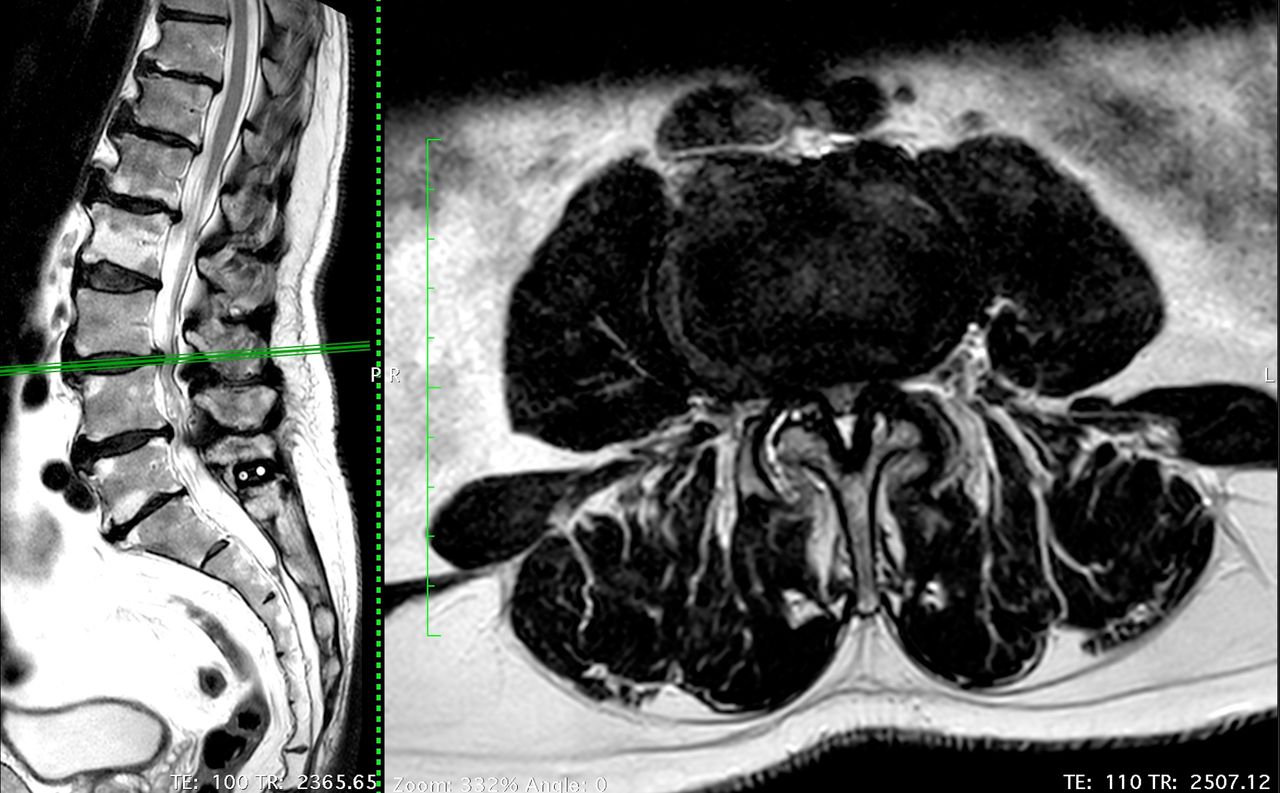

Da diversi anni mi occupo di pazienti con patologie, degenerative, tumorali e traumatiche del rachide. La necessità di prendermi cura di questi malati mi ha portato, durante la mia formazione e ancora oggi, ad acquisire competenze riguardanti non solo le più moderne tecniche chirurgiche, ma anche procedure di terapia del dolore, infiltrative e riabilitative.

Sono un Neurochirurgo e Chirurgo Vertebrale; il mio focus principale consiste nel trattamento del mal di schiena, condizione tanto comune, quanto difficile da diagnosticare con precisione e da trattare, e in generale di tutte le condizioni dolorose acute e croniche legate alla colonna vertebrale.

Sono specializzato anche nel trattamento delle deformità dell'adulto, quali la scoliosi e lo sbilanciamento sagittale, che tratto con tecniche mini-invasive e approcci anteriori e laterali (ALIF e XLIF rispettivamente), in grado di non violare la muscolatura e garantire un rapido decorso post-operatorio, diminuendo il dolore legato agli accessi chirurgici. Utilizziamo di routine il monitoraggio neuro-fisiologico per ridurre al minimo il rischio di danni ai tessuti nervosi.